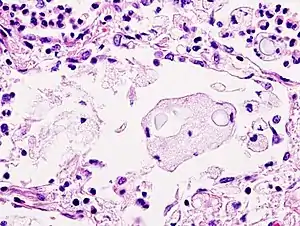

Mucicarmine stain: bright pink cryptococcosis capsule[33]

Biopsy

A special stain may be needed to see the cryptococcus capsule.[33]